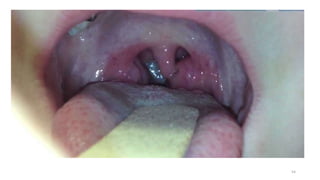

PERITONSILLAR ABSCESS

• Examination of the pharynx reveals medial displacement of the soft

palate, tonsil, and uvula.

• Antibiotics are given as for a retropharyngeal abscess